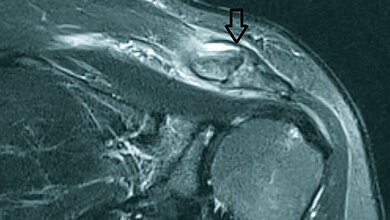

Anomalien und Normvarianten: Skelettale Veränderungen 3.29: Brachydaktylie und Brachymetacarpie

Die Brachydaktylie ist Teil einer Gruppe der Gliedmaßen-Malformationen mit Knochendysostosen. Die isoliert auftretende Brachydaktylie ist selten. Sie kann mit anderen Fehlbildungen der Hand einhergehen, wie zum Beispiel Syndaktylie oder Polydaktylie.

Schlüsselwörter: Brachydaktylie, Röntgen, CT, MRT